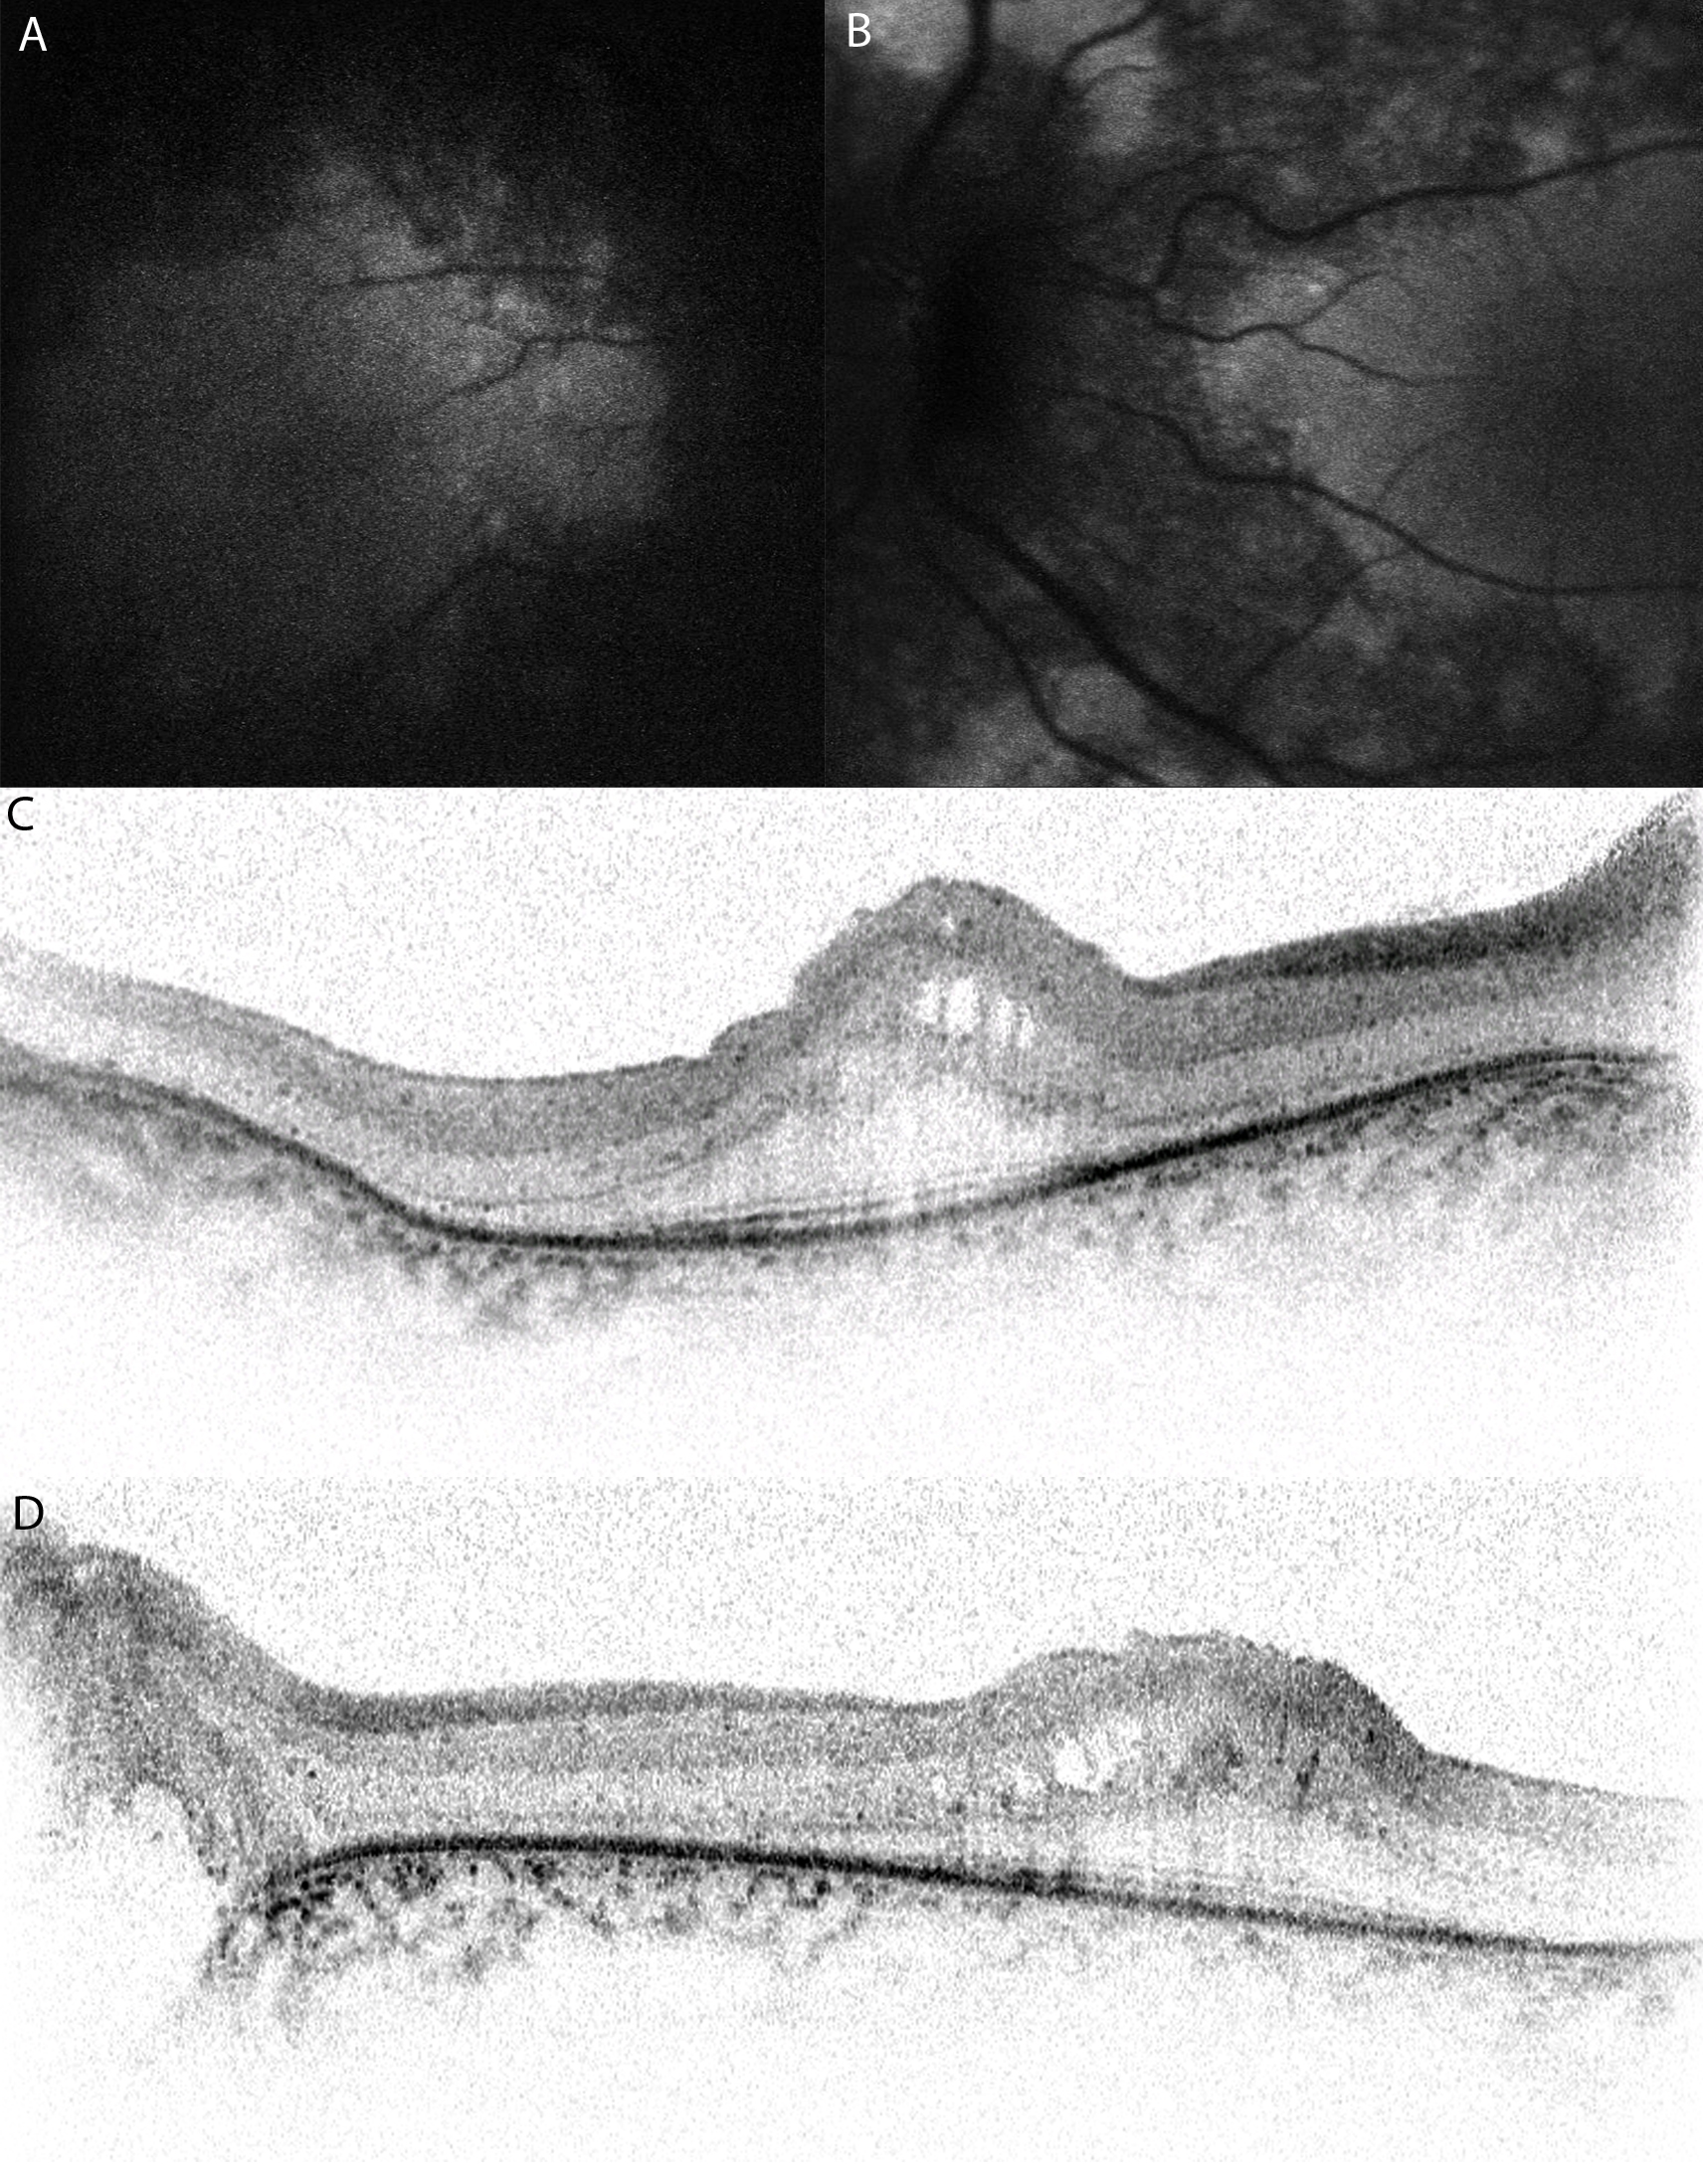

Figure 2. Autofluorescence images and

high-resolution spectral domain optical coherence tomograms of affected

patients with membrane-type frizzled-related protein, and related

oculopathy. Autofluorescence images of the right (A) and left (B)

eyes

of posterior pole of individual III-1 of family 4 show relative

preservation of the central macula. Optical coherence tomograms of the

right (C) and left (D) fovea of individual II-1 of family

3 show areas of low reflectivity, which are due to cysts and relative

thickening of the retina in the foveal region.